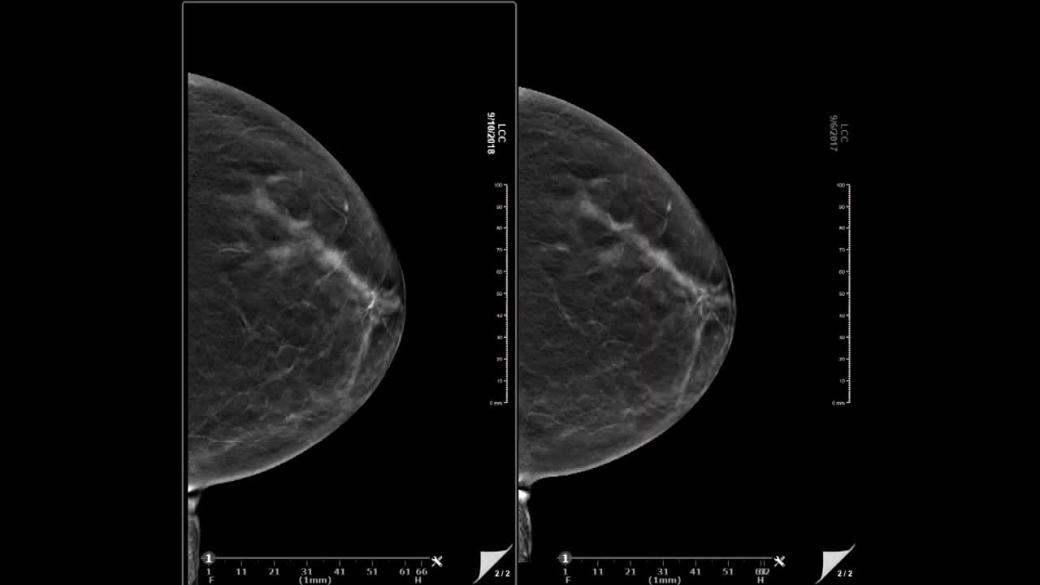

曼尼托巴省政府宣布了一个月内第二次扩大乳腺癌筛查的计划。

卫生部长佐佐马·Asagwara表示,到2026年12月,自行转诊的最低年龄将降至40岁。

新民主党政府上个月表示,到明年年底,退休年龄将从目前的50岁降至45岁,并承诺最终将在某个未指明的日期降至40岁。